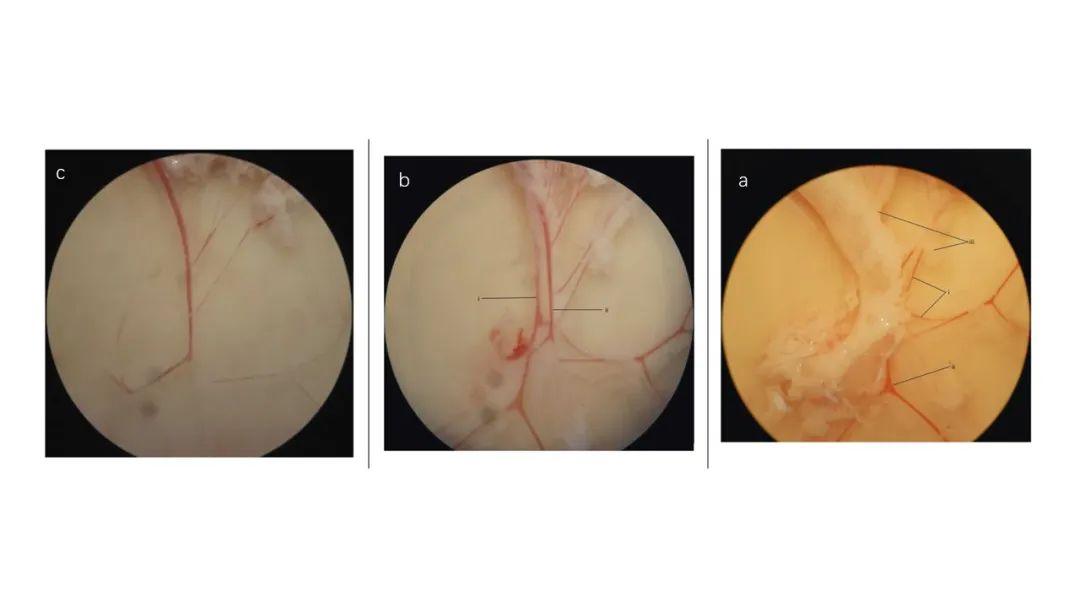

腸系膜血管解剖顯微鏡下圖像。(a)去除結(jié)締組織和神經(jīng)束前,可見(jiàn)(i)動(dòng)脈、(ii)靜脈和(iii)粘附脂肪。(b)切除大部分結(jié)締組織和神經(jīng)束后。(i)位于(ii)靜脈下方的動(dòng)脈比后者顯得“更白”。(c)清潔的動(dòng)脈。